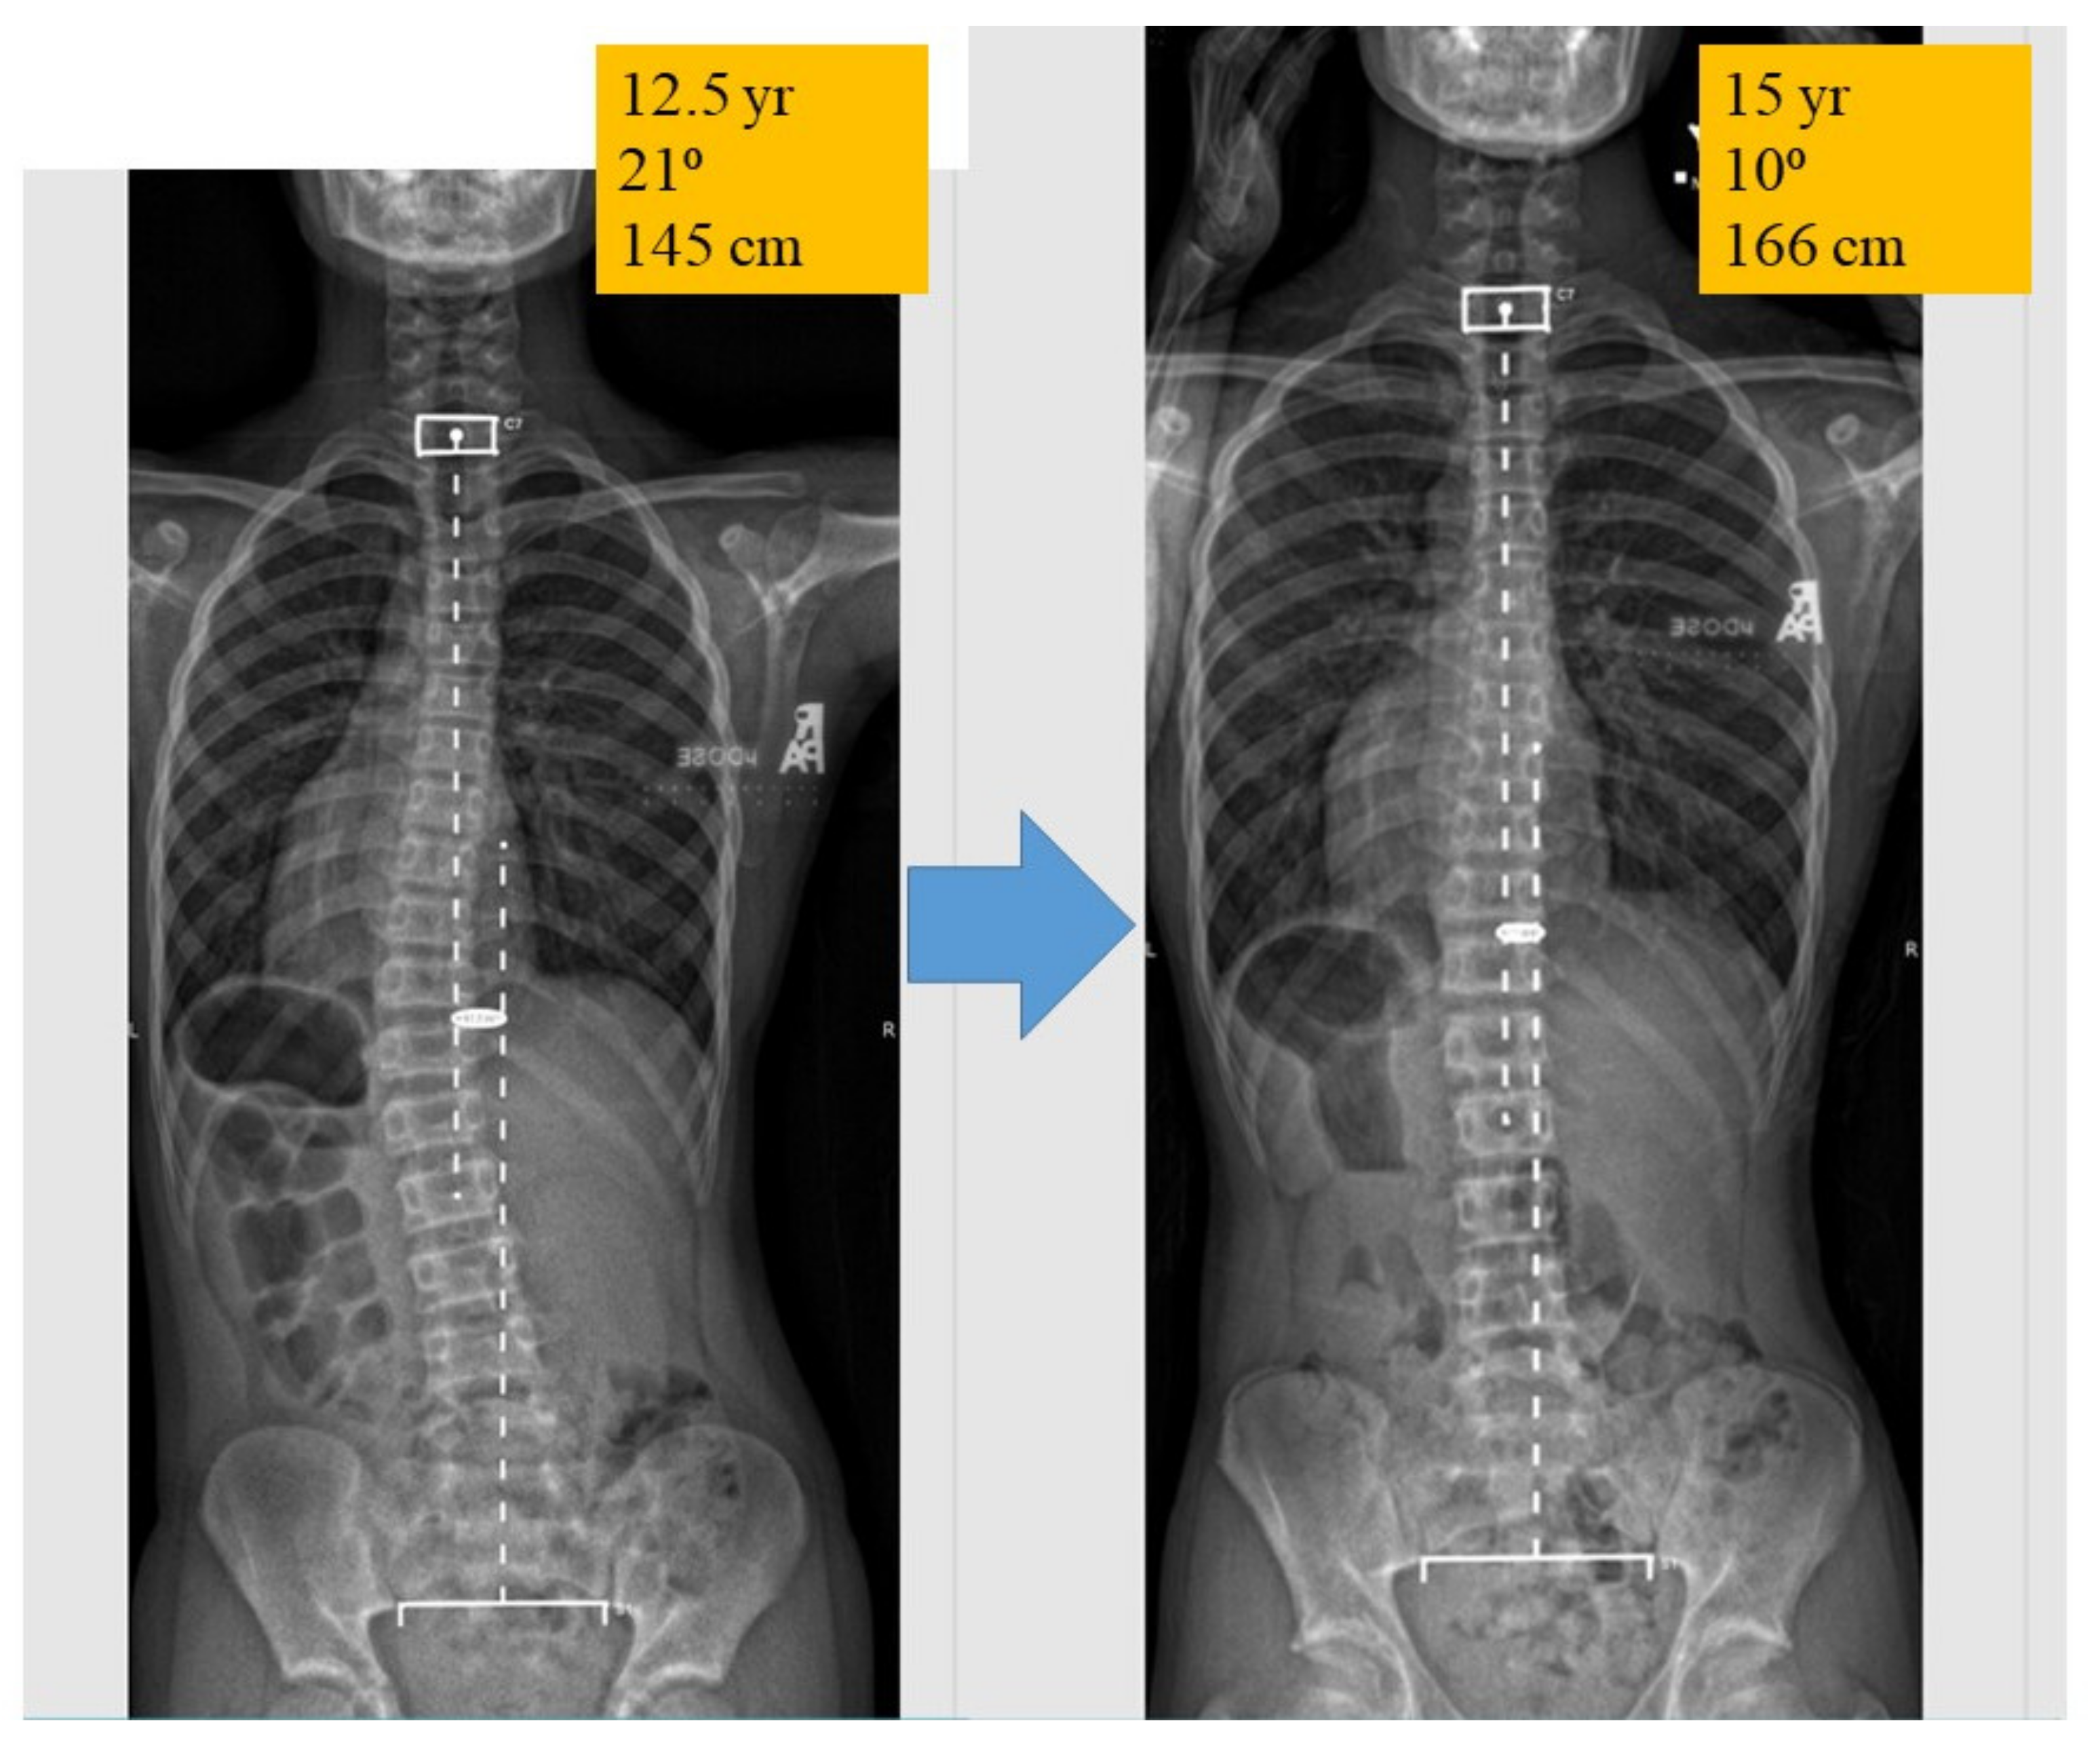

4. AIS Delineated into 2 Phases: Initiation and Progression